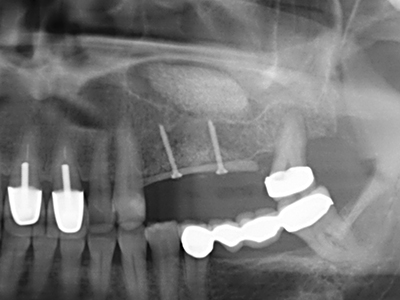

Die Präparation des lateralen Fensters bei der externen Sinusbodenelevation stellt gerade für chirurgisch unerfahrene Implantologen eine große Herausforderung dar. Die knöcherne Bedeckung der Kieferhöhle ohne eine Verletzung der darunterliegenden Schneider’schen Membran abzutragen ist dabei nur ein Teil der Operation – nach Schaffung eines ausreichenden Zugangs muss die Kieferhöhlenschleimhaut vorsichtig mobilisiert werden, um Raum für das einzubringende Material bzw. die Implantate zu schaffen. In dieser Indikation ist die Piezochirurgie zweierlei hilfreich: zum einen kann durch Verwendung diamantierter Instrumente eine selektive Knochenabtragung erfolgen und die darunter liegende Schleimhaut bleibt bei vorsichtiger Vorgehensweise intakt. Zum anderen unterstützen die Ultraschallfrequenzen zusätzlich eine komplikationslose Ablösung der Schleimhaut – sie werden durch spezielle stumpfe Ansätze in den Spaltraum zwischen Schleimhaut und Kieferhöhlenboden übertragen (Cassetta, Ricci et al. 2012, Pereira, Gealh et al. 2014) (Rickert, Vissink et al. 2013). So erscheint es nicht verwunderlich, dass in aktuellen Übersichtsarbeiten über die externe Sinusbodenelevation neben der Verwendung von rauen Implantatoberflächen und dem Einsatz von Knochenersatzmaterialien auch der Einsatz von piezoelektronischen Geräten als positiv bewertet wird (Wallace, Tarnow et al. 2012).

Bei der Knochenblockentnahme zeigen sich weitere Vorteile für die Piezochirurgie: Neben der bereits beschriebenen hohen Präzision bei der Osteotomie stellt sich gerade die Verwendung der dünnen Sägespitzen als besonders materialschonend heraus. Bei der Verwendung insbesondere von Lindemannfräsen sind mit deutlich höheren Entnahmeverlusten durch die dickere Instrumentenspitze zu rechnen (Lakshmiganthan, Gokulanathan et al. 2012). Die insbesondere bei retromolar entnommenen Blocktransplantaten notwendige basale Abtrennung wird durch speziell hierfür vorgesehene rechtwinklige Sägen erleichtert, so dass die Piezochirurgie als präzises, übersichtliches und sicheres Verfahren zur retromolaren Knochenblockgewinnung angesehen wird (Happe 2007) (Abb. 1-12).

Knochengewebe ist nicht nur rein mineralisch, sondern auch in wesentlichen Anteilen aus Kollagenfasern aufgebaut. Dies gewährleistet neben einer guten Druckfestigkeit eine gewisse Flexibilität, welche für die Durchführung von Augmentationen genutzt werden kann. Bei der klassischen Expansionsplastik im Sinne eines Bone Splittings wird der atrophierte Kieferkamm in seiner Längsachse gespalten und nach Erreichen einer ausreichenden Osteotomietiefe vorsichtig aufgedehnt (Abb. 13-16), idealerweise ohne den Kiefer wesentlich zu deperiostieren (Brugnami, Caiazzo et al. 2014, Stricker, Fleiner et al. 2014). Bewährt haben sich Schrauben- und Plattensysteme mit zunehmender Expansionsdistanz, um die beiden Knochenlamellen unterhalb der Bruchschwelle voneinander zu distanzieren. In der Regel werden Restknochenbreiten von mindestens 3-4 mm gefordert (Chiapasco, Zaniboni et al. 2006), um eine ausreichende Flexibilität und knöcherne Bedeckung der einzubringenden Implantate zu gewährleisten. Ggf. kann eine ein- oder beidseitige vertikale Entlastungsosteotomie die Flexibilität verbessern. Als Alternative zur klassischen Technik wurde eine Kombination mit weiteren augmentativen Techniken vor allem auf der bukkalen Seite beschrieben.

Mittels Piezosägen erfolgt die Anlage des Splittings besonders schonend und ohne wesentliche Dimensionsverluste, so dass sich keine signifikanten Unterschiede von Implantaten im gesplitteten Kiefer im Vergleich zum nicht defizitären Alveolarkamm gezeigt haben (Chiapasco, Zaniboni et al. 2006, Danza, Guidi et al. 2009). Gerade beim lokal begrenzten und tiefen Splitting ist jedoch stets auf eine ausreichende Wasserkühlung zu achten, um thermische Belastungen in den apikalen Osteotomiebereichen zu vermeiden.